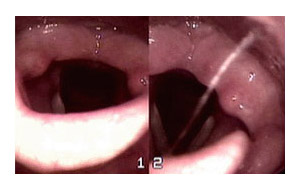

ȨÀ¸·Î ¸ÆÀ̺óÀÎÈİú µÚ·Î

¿ª·ù¼ºÈĵο°